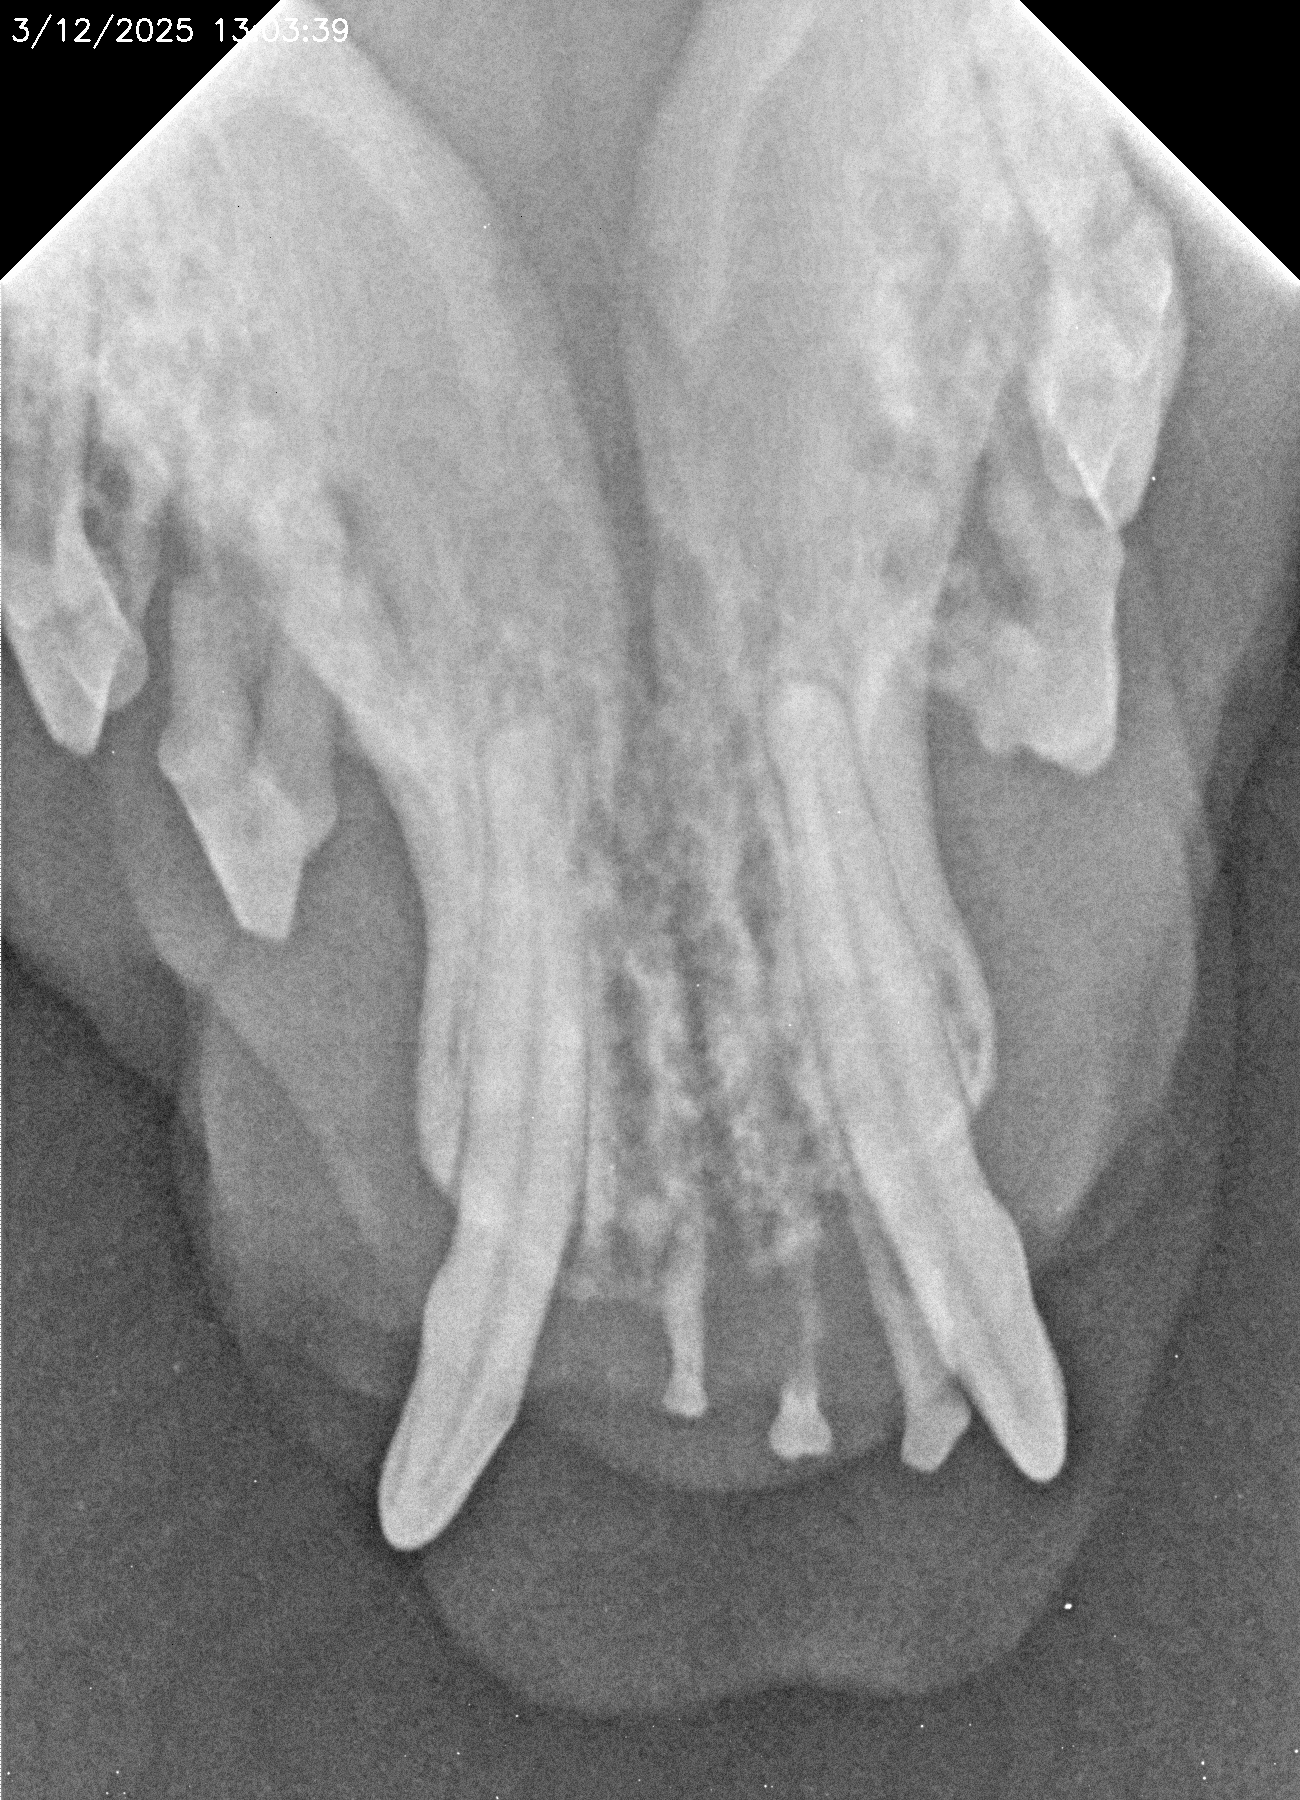

La salud bucal en animales es fundamental para su bienestar general. Los problemas dentales más comunes, como las infecciones bucales, las encías inflamadas o los dientes en mal estado, no solo provocan mal aliento y dolor, sino que pueden causar complicaciones más serias. Cuando se dejan sin tratamiento, las bacterias orales pueden llegar al torrente sanguíneo y afectar órganos importantes como el corazón, los riñones y el hígado.

Al igual que en los humanos, la higiene dental regular es esencial para prevenir enfermedades periodontales y otros problemas dentales. Los animales que sufren de dolor bucal pueden volverse más irritables, perder el apetito y, en algunos casos, experimentar dificultades para comer o masticar.